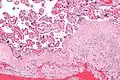

Micrograph of chronic deciduitis. H&E stain.

Acute choriodeciduitis, with neutrophils seen in the chorion and decidua.